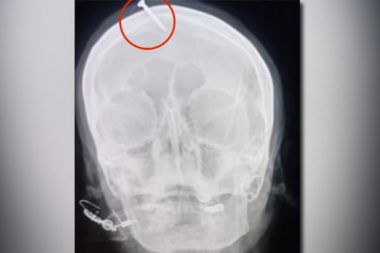

Viruela del mono: Hallan ADN de virus en semen

Encontraron restos en pacientes italianos heraldodemexico.com.mx Fragmentos del virus de la viruela…